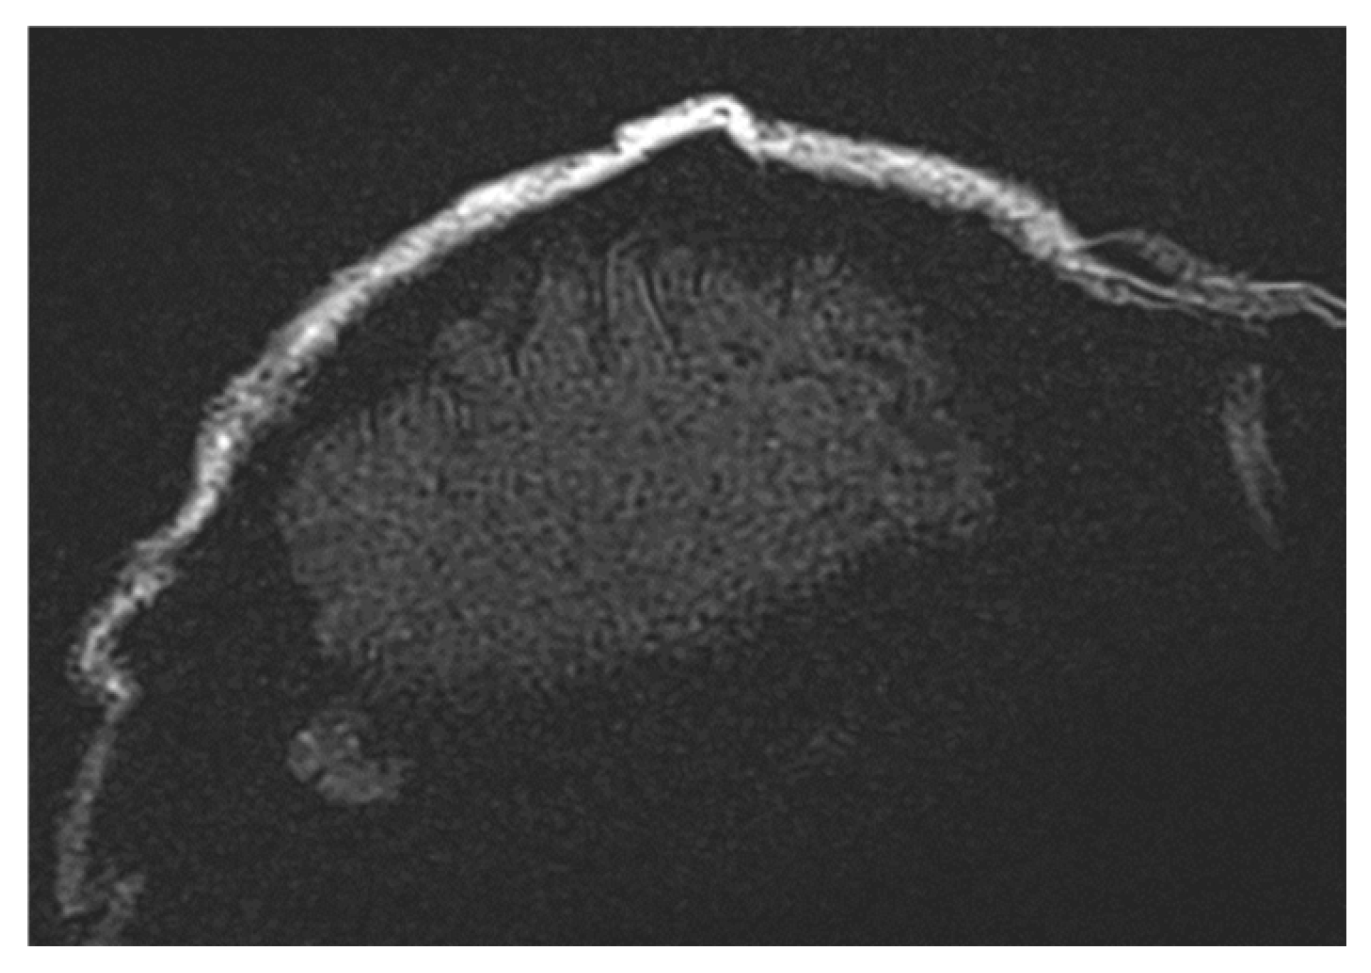

3.1. Types and Causes of MRI Artifacts

3.2. Artifact Suppression Techniques

3.4. Turbo Spin Echo (TSE) for Artifact Reduction

3.6. Optimized Imaging Sequences for Tumor Detection Under Cranial Implants